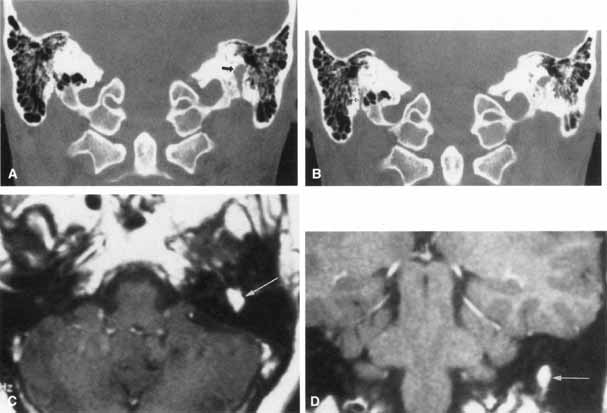

A history of cancer (particularly involving the breast, lung, thyroid, kidney, ovary, or prostate) associated with a rapidly progressive facial paralysis strongly suggests a metastatic lesion. The facial nerve may be involved by a bony metastasis or by meningeal infiltration. Neuroimaging studies are indicated to search for the primary site and to localize the site of facial nerve involvement (Fig. 17). If these are unrevealing, serial lumbar punctures may be necessary to exclude meningeal carcinomatosis. In some cases, surgical exploration of the temporal bone or of the extracranial course of the facial nerve is recommended to locate the lesion. In one study of meningeal carcinomatosis, the seventh nerve was affected in 15 of 90 patients.95 Facial nerve involvement is often unilateral, but it occurs bilaterally in about 10% of such patients.96

Fig. 17 Axial MRI scan discloses idolinium enhancement and enlargement of right facial nerve (arrow) in patient with meningeal carcinomatosis.